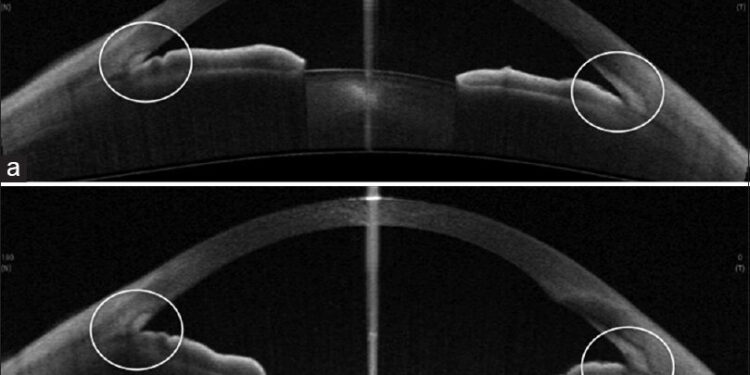

Σύμφωνα με το άρθρο με τίτλο “Bisphosphonate Use Linked to Increased Risk of Acute Angle Closure”, μια πρόσφατη μελέτη υποδεικνύει μια στατιστικά σημαντική συσχέτιση μεταξύ της χρήσης διφωσφονικών και του αυξημένου κινδύνου οξέος γλαυκώματος κλειστής γωνίας. Το οξύ γλαυκώμα κλειστής γωνίας είναι μια επείγουσα οφθαλμολογική κατάσταση που χαρακτηρίζεται από απότομη αύξηση της ενδοφθάλμιας πίεσης, η οποία μπορεί να οδηγήσει σε σοβαρή απώλεια όρασης εάν δεν αντιμετωπιστεί άμεσα.

Ο ακριβής μηχανισμός μέσω του οποίου τα διφωσφονικά μπορεί να αυξάνουν τον κίνδυνο οξέος γλαυκώματος κλειστής γωνίας δεν είναι πλήρως κατανοητός. Ωστόσο, υπάρχουν διάφορες θεωρίες. Μια πιθανή εξήγηση είναι ότι τα διφωσφονικά μπορεί να επηρεάζουν τη δομή ή τη λειτουργία του ακτινωτού σώματος του οφθαλμού, το οποίο είναι υπεύθυνο για την παραγωγή και την αποχέτευση του υδατοειδούς υγρού. Μια διαταραχή σε αυτή τη διαδικασία θα μπορούσε να οδηγήσει σε αύξηση της ενδοφθάλμιας πίεσης και, κατ’ επέκταση, σε οξύ γλαύκωμα κλειστής γωνίας.